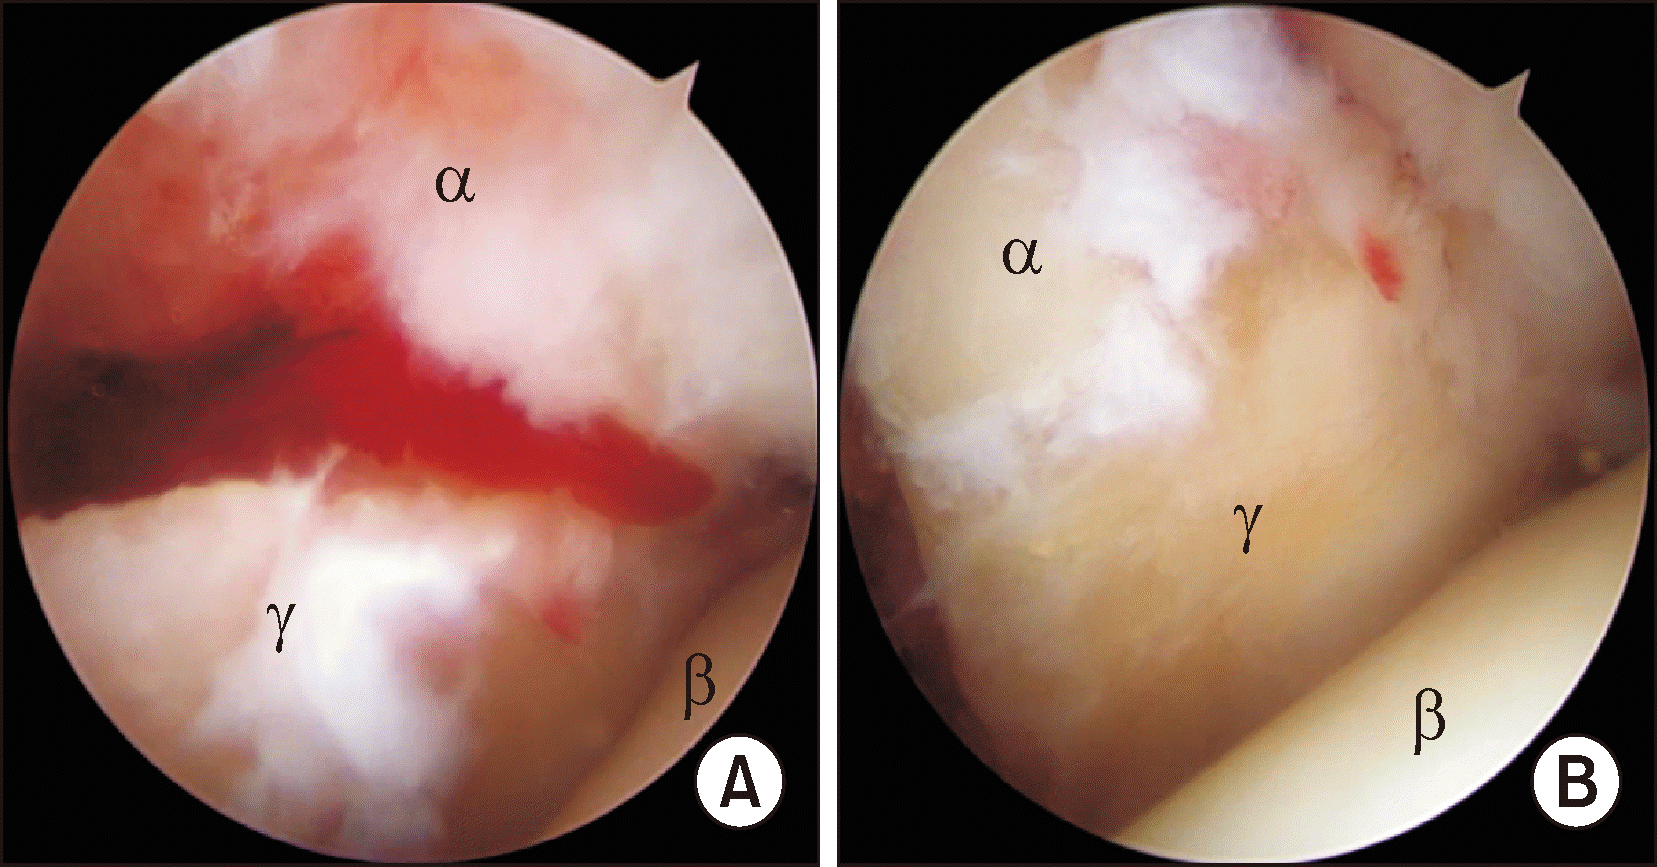

Figure 1

Anteroposterior (A) and lateral (B) radiographs shows Danis-Weber type C lateral malleolar fracture. Plain radiographs do not show obvious osteochondral lesions. Arthroscopy shows a loose body (C) and osteochondral lesion of the medial talar dome (D). αLoose body, βTibia, γTalus, δOsteochondral lesion.